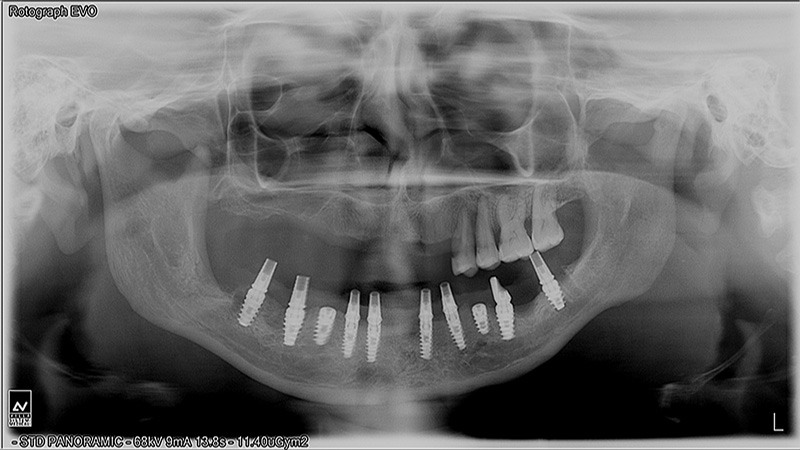

Implants

Implant Patients